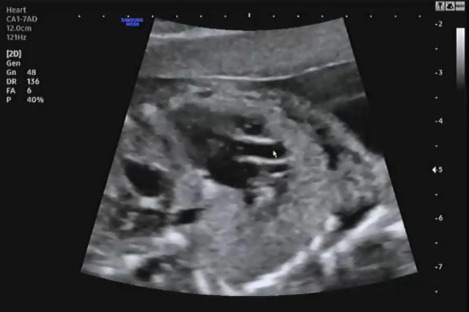

그다음 양측 귀를 확인했다. 왼쪽은 귀가 있는 것을 명확히 확인하고 반대편을 확인하는데 햇님이가 손을 올리고 귀를 가렸다. 초음파로 여기저기 확인하며 겨우 양측 모두 귀가 형성된 것을 확인했다.